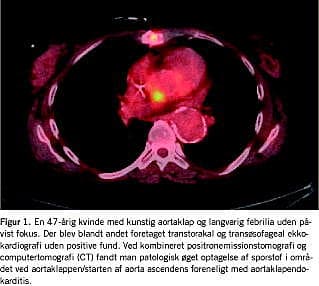

Feber af ukendt årsag

Feber af ukendt årsag (FUO) kan være en klinisk og diagnostisk udfordring (Figur 1 ). Tilstanden blev første gang defineret i 1961 af Robert G. Petersdorf et al som febrilia over 38,3 °C ved mindst to lejligheder i en periode på 2-3 uger og uafklaret diagnose efter en uges indlæggelse. Sidstnævnte er siden revideret til manglende diagnose trods passende udredning. Populært angives det, at de mulige årsager kan være infektion, okkult malign lidelse og autoimmun inflammatorisk systemsygdom med omtrent samme hyppighed, men i op mod en tredjedel af tilfældene stilles en endelig diagnose ikke trods omfattende udredning. FDG PET giver mulighed for helkropsskanning med et sporstof, der potentielt akkumuleres i alle tre tilfælde, hvorfor sensitiviteten teoretisk set er høj, mens specificiteten er tilsvarende begrænset [1]. Dette kan dog opfattes positivt, idet udredningens primære formål er at påvise og lokalisere uanset ætiologi. Der er kun publiceret seks studier med FDG PET (n = 16-74), som er samlet i en nyere oversigtsartikel [1]. Selvom studiedesign, patientpopulationer og resultatopgørelse er varierende, synes resultaterne lovende: PET bidrog positivt til diagnosen i 25-87% af tilfældene, og teknikken spås et betydeligt potentiale, specielt i kombination med CT. En særlig fordel ved kombineret FDG PET/CT er, at man opnår informationerne med en enkelt undersøgelse i modsætning til den gængse diagnostiske strategi, der ofte involverer en række forskellige modaliteter, der er fordelt på flere undersøgelsesdage.